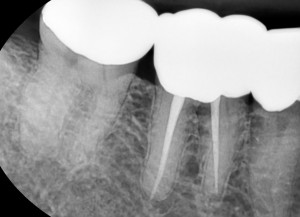

치료 받은지도 4~5년이나 되었다고 하셔서 작은 방사선 사진을 찍어보기로 하였습니다.

치아 해부 구조상 신경관은 매우 가늘고 복잡하게 생겨있기에

드물지만 해당 치아의 신경관 중 하나가 치료가 안 된 경우도 있습니다.